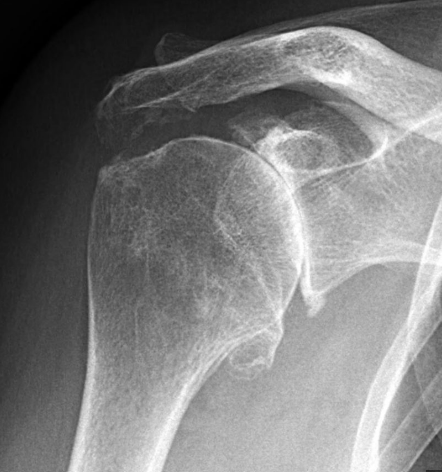

Une radiographie simple d'épaule permettra de diagnostiquer l'omarthrose. On pourra observé un pincement de l'interligne articulaire, des ostéophytes et des géodes

Omarthrose

L'arthrose est l'usure de l'articulation et la disparition du cartillage